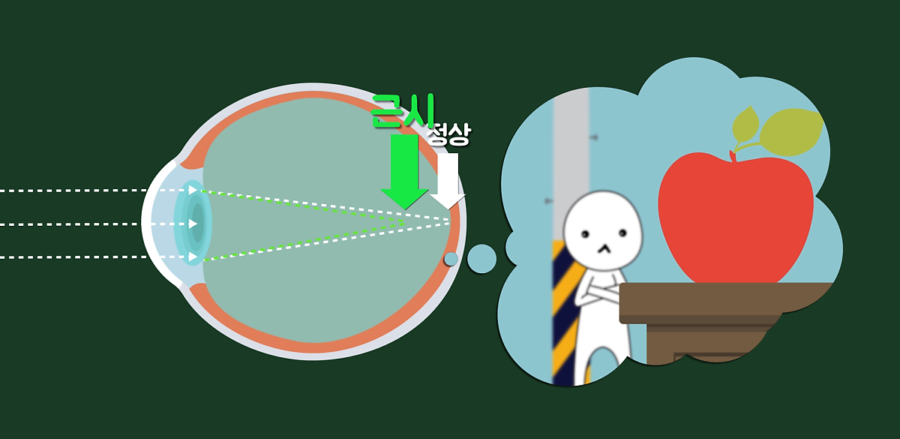

자세히 알아보면 근시는 안구의 굴절이상 중의 하나로 망막에 맺혀야 할 상이 망막보다 앞쪽에 맺히는 증상입니다. 안구 길이가 각막과 수정체의 초점 거리보다 길면 발생하고, 이러한 근시는 오목렌즈로 상을 퍼지게 해서 뒤쪽에 맺히도록 교정해줍니다.

원시도 눈의 굴절이상 중의 하나로 망막에 맺혀야 할 상이 안구의 뒤쪽에 맺히는 증상입니다. 안구 길이가 각막과 수정체의 초점거리보다 짧으면 발생하고, 이러한 원시는 볼록 렌즈를 통해 상을 모아주어 앞쪽에 맺히도록 교정해줍니다. 그리고 난시는 빛이 각막에서 굴절하면서 상이 한 점에 맺히지 못하고 불규칙적으로 맺히는 증상으로 상이 가깝거나 멀리 있을 때 모두 흐릿하게 보입니다.